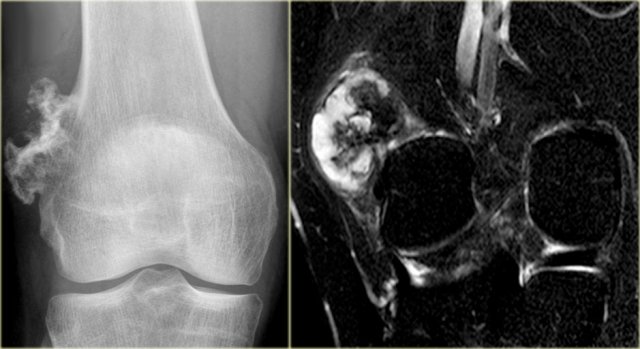

Chondroblastoma (7)

The images show a chondroblastoma in the patella.

Notice the extensive edema (blue arrow)

Chondroblastoma (8)

Here lesion in the proximal tibia in a 20 year old.

Key findings:

• Epiphyseal lesion

• Lobulated margins

• Extensive edema

• Young patient.

Diagnosis: Chondroblastoma.

Diff. diagnosis: Osteomyelitis.

Chondroblastoma (9)

What are the findings:

• Well-defined osteolytic lesion in the talus.

• No matrix formation.

• Subtle reactive sclerosis.

• T2-WI with FS shows typical extensive peritumoral edema in the entire bone.

• High uptake on bone scintigraphy.

The talar bone is one of the preferential sites for chondroblastoma.